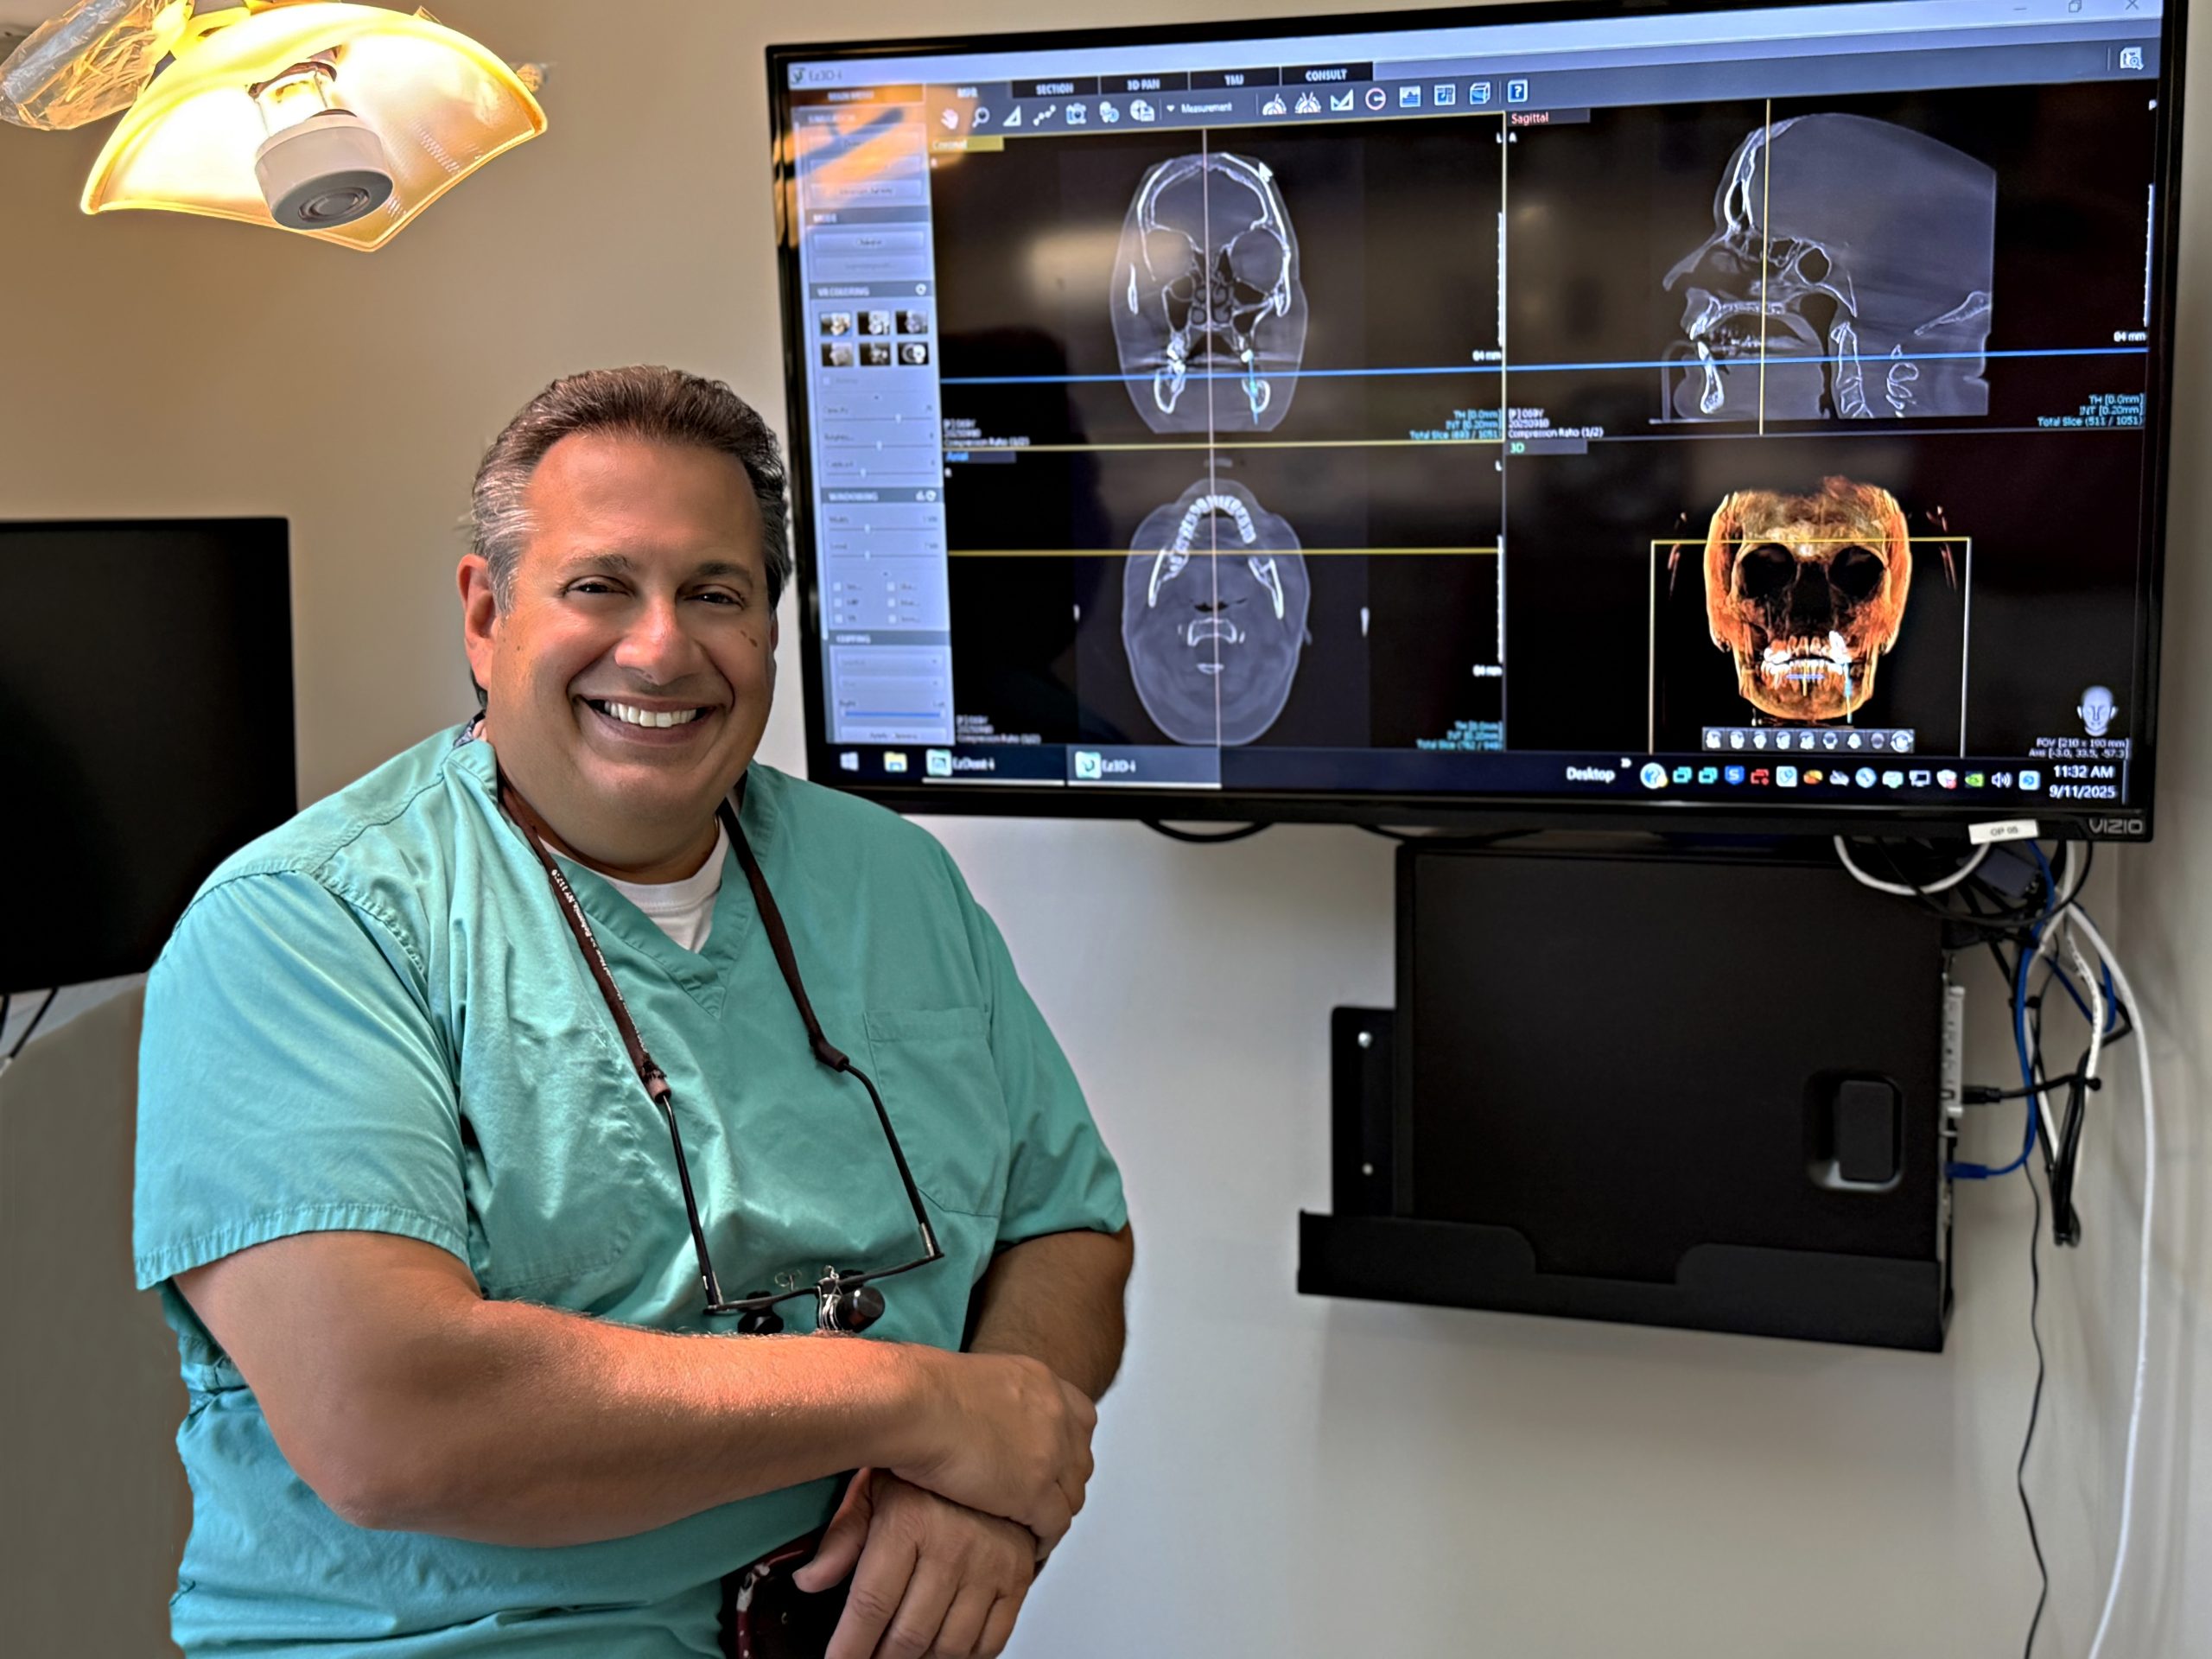

Dr. Dante E. Gulino, Jr.

View More

At our practice, we are committed to providing personalized, patient-centered care. We recognize that each individual’s treatment plan is unique, and we give it the careful attention it deserves. Dr. Gulino’s compassionate demeanor, coupled with his extensive knowledge and experience, ensures that every patient feels at ease throughout their treatment. Our offices are equipped with the latest technology, allowing us to continually enhance our care and offer the best possible outcomes for you.